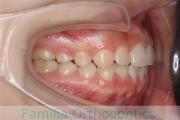

歯並びを治したいということで来院されました。下あごがやや右側に偏位して後退している、上顎前突(出っ歯)でした。上下左右から小臼歯を抜歯して、歯科矯正用アンカースクリューを併用したマルチブラケット法にて治療を行いました。約2年、24回の来院をしていただきました。

下顎の後退はいびきなどの上部気道の障害が出やすいと考えられます。